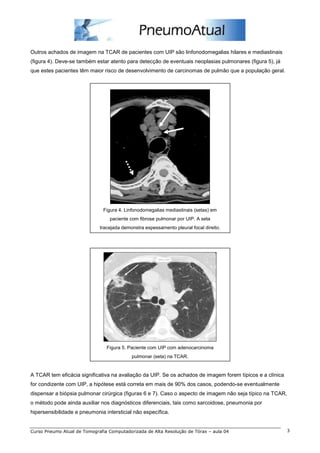

Figura 6. Paciente com achados clássicos de UIP na TCAR, com alterações intersticiais e sinais de fibrose nas bases,

caracterizados por opacidades em vidro fosco, reticulado, espessamentos septais e bronquiolectasias de tração. O

paciente era portador de esclerodermia (a seta aponta para dilatação esofágica na TCAR) e não foi necessário realizar

biopsia pulmonar cirúrgica.

Figura 7. Alterações intersticiais nos lobos inferiores de paciente em uso de amiodarona. Pneumonia intersticial usual,

caracterizada por opacidades em vidro fosco, espessamentos septais irregulares e bronquiolectasias de tração com

distorção da arquitetura pulmonar.